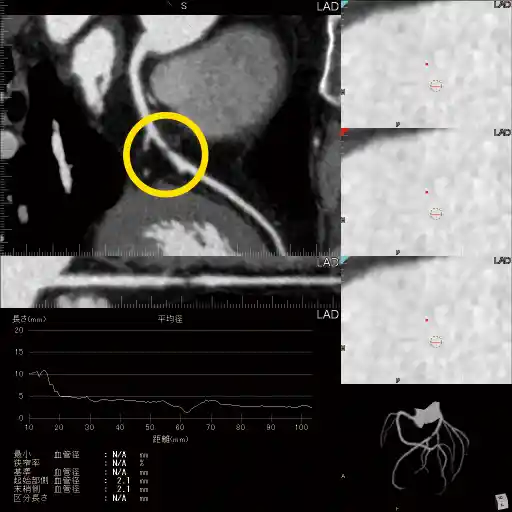

心疾患(心筋梗塞)は日本人死因の第2位で、働き盛りの人の突然死で最も多く、その内3割は前兆もなく突然に発症しています。

冠動脈CT(マルチCT)で冠動脈の狭窄の状態を把握して心筋梗塞を予防します。